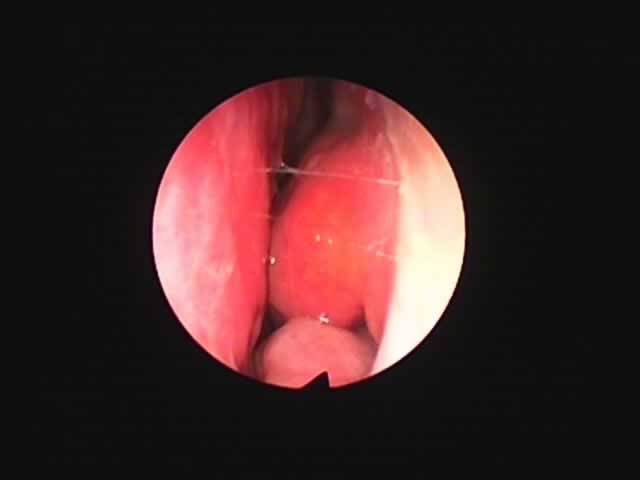

![]() |

| 7月16日 かなり縮小 | 両手術直後(縮小不十分なため追加焼灼、8月9日) | 9月8日 著明に縮小しいびき消失しているとのことです |